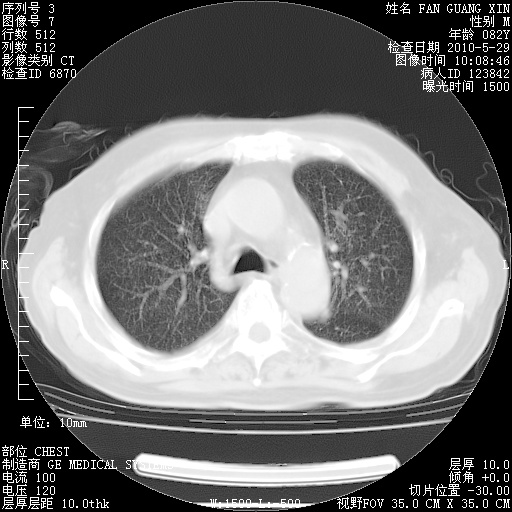

再治疗10天后的肺部CT